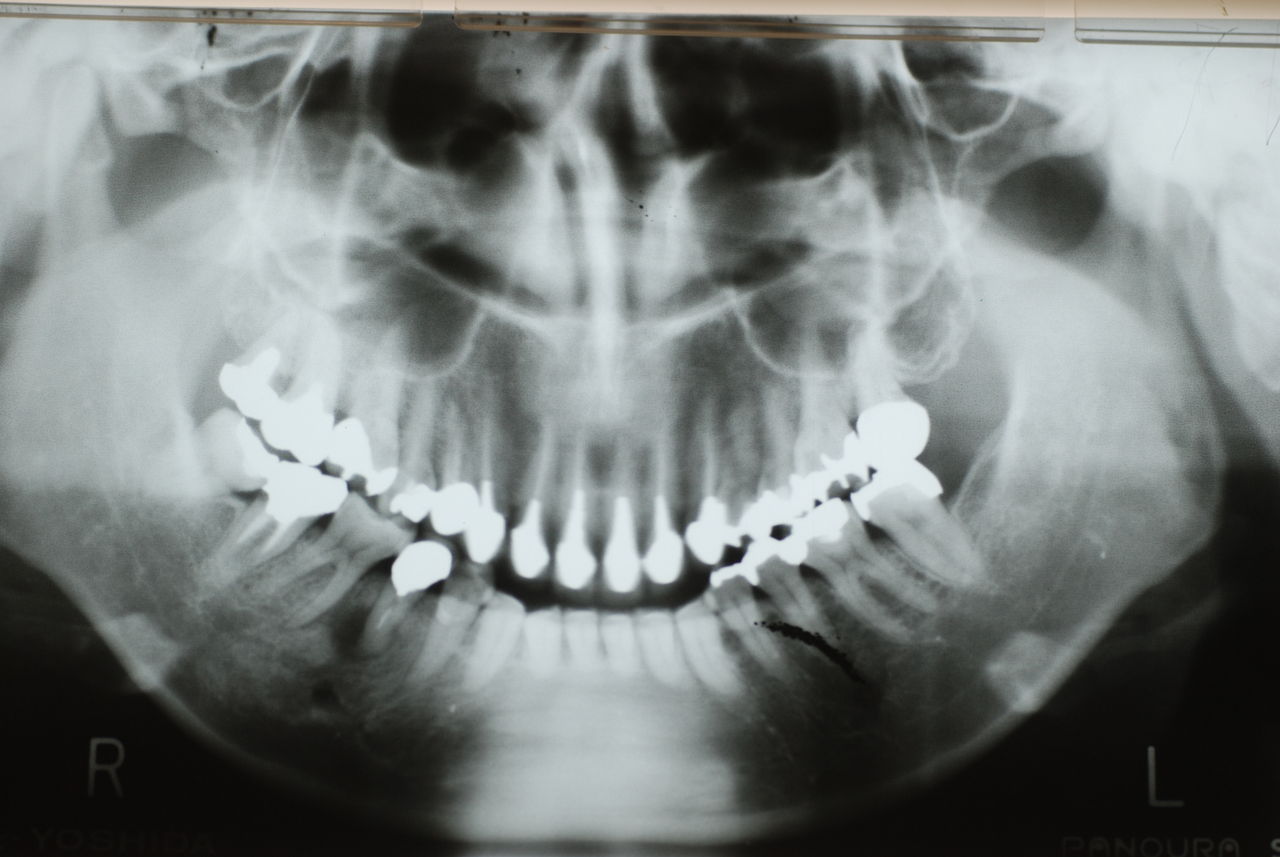

下の歯は数本存在しますが、全て虫歯と歯周病に犯されていました。

食べカスまみれで歯周病に罹患しています。